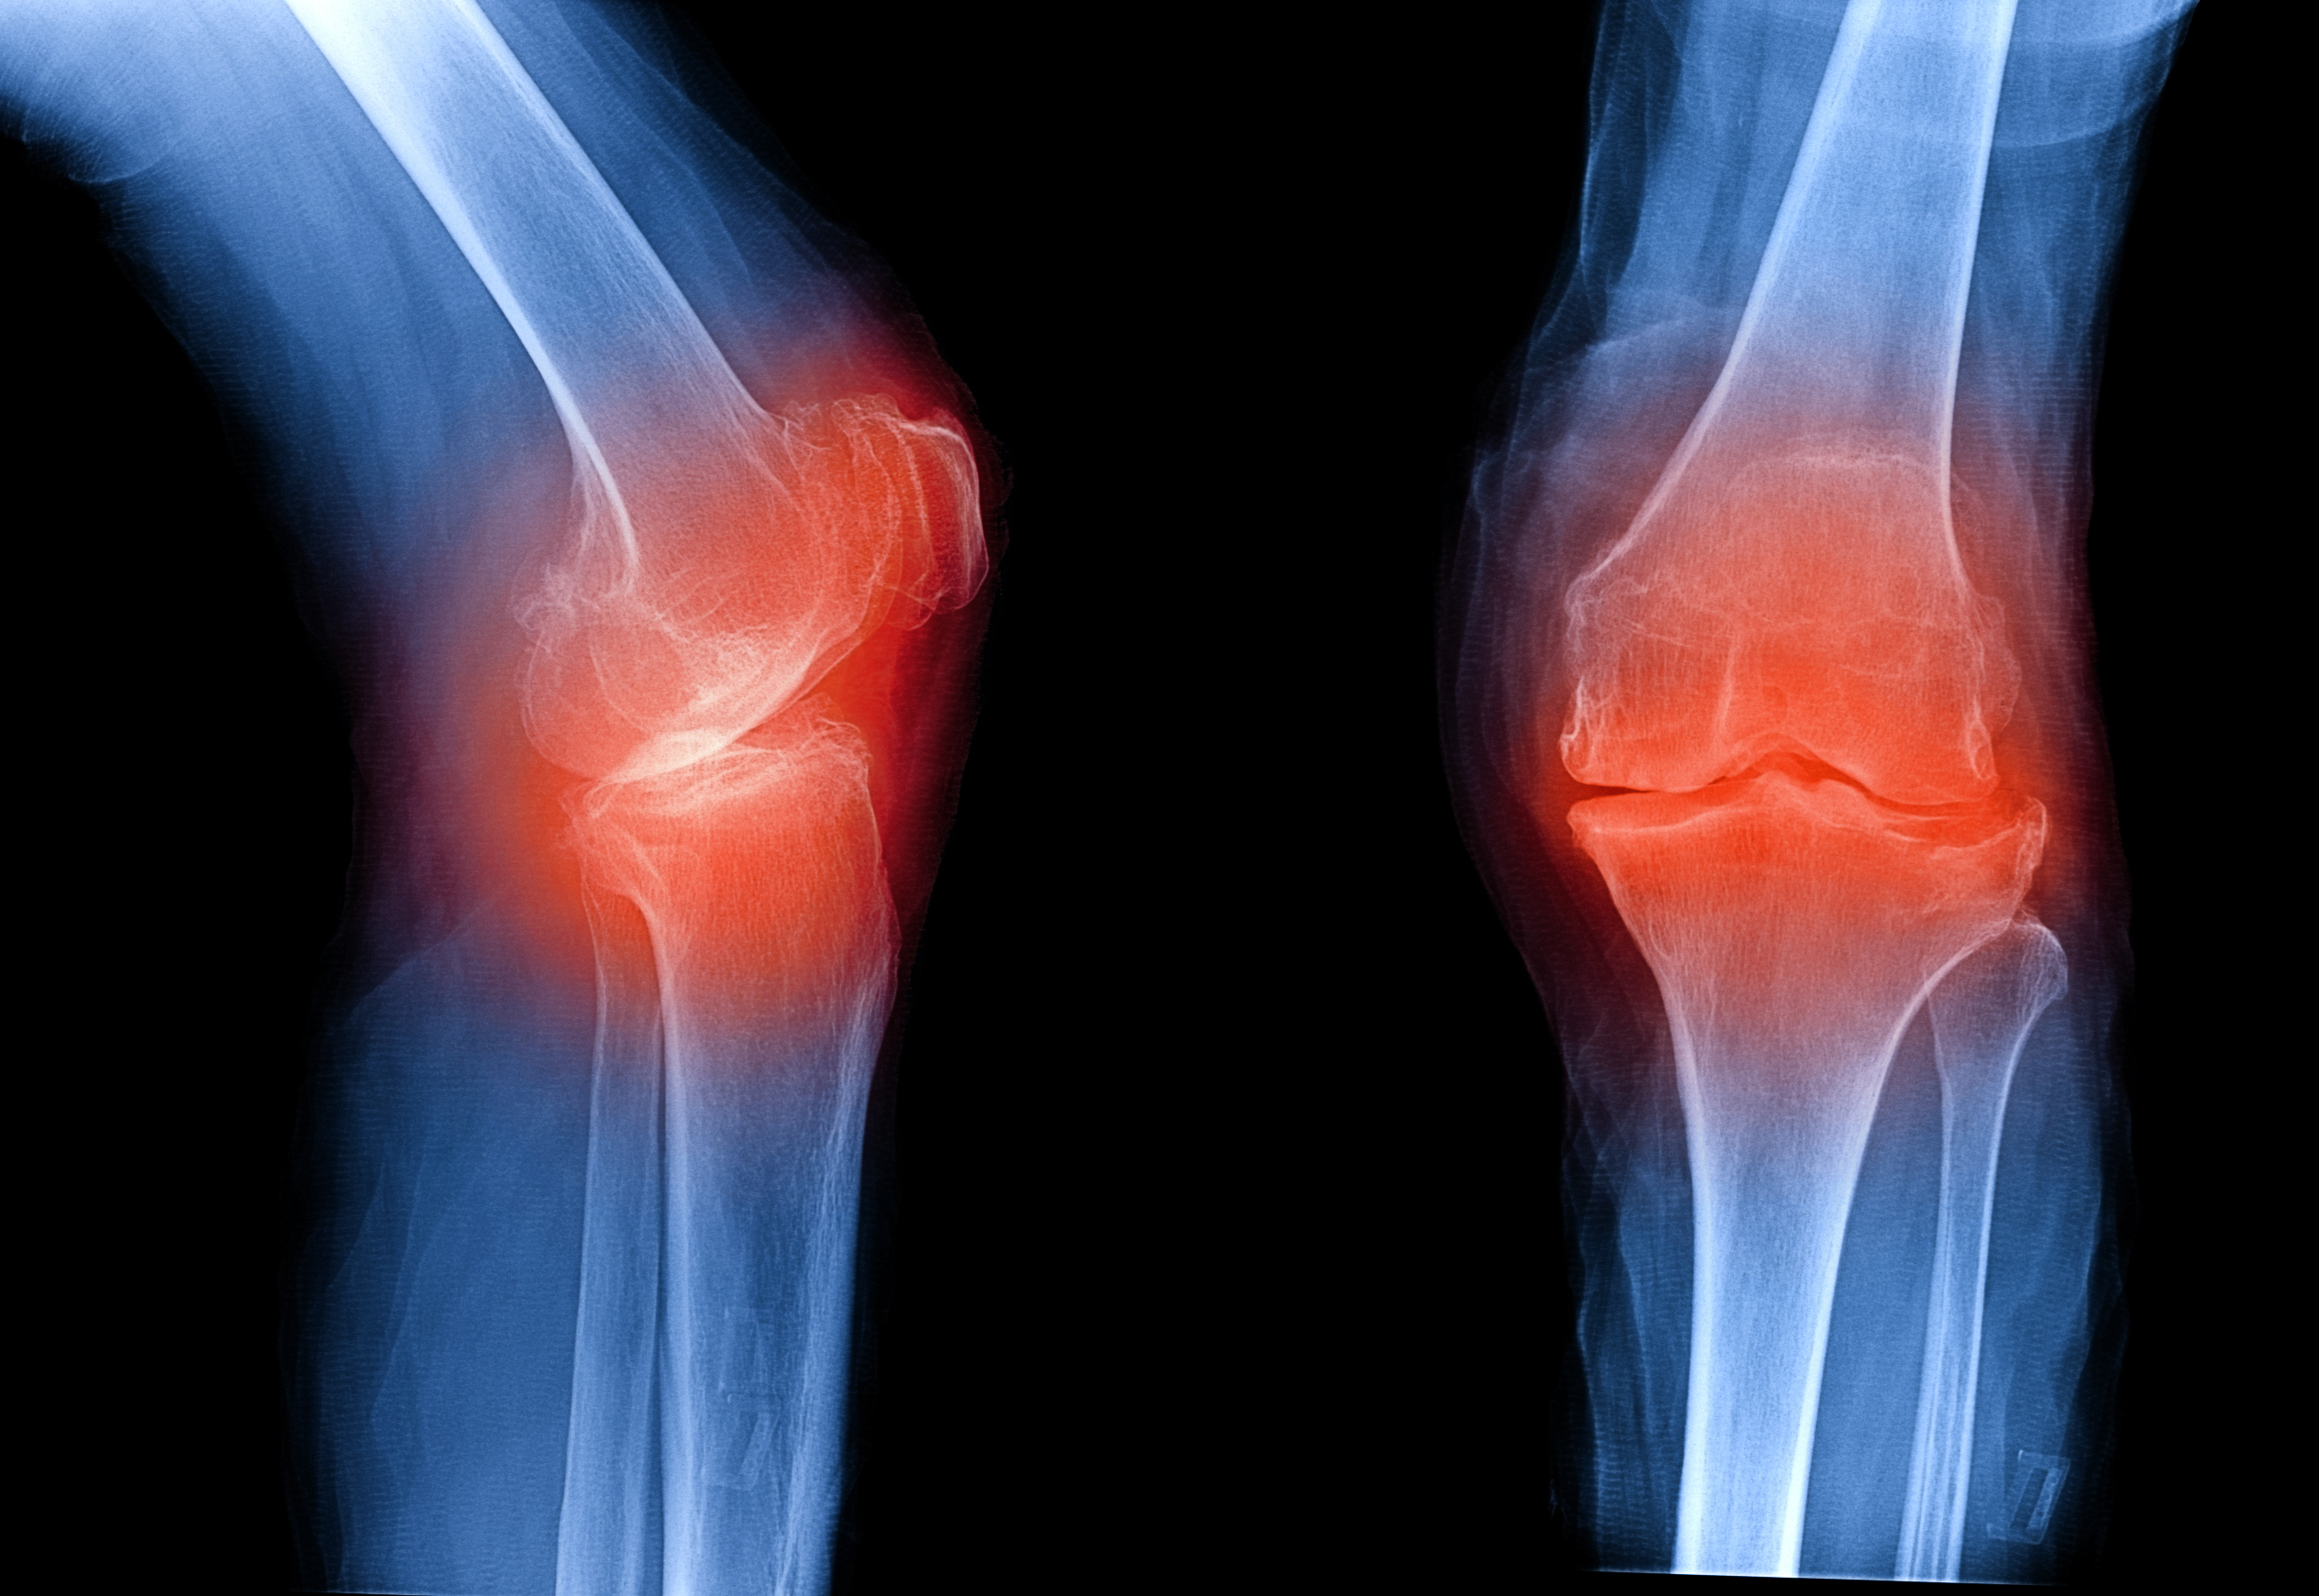

Медицинские снимки: рентген коленного сустава при остеопорозе